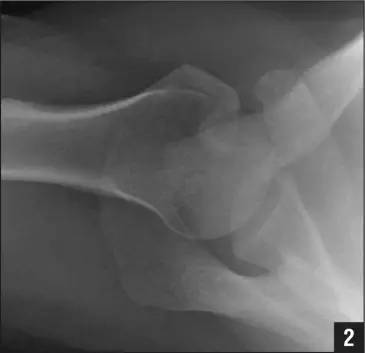

侧位片示反 Hill-Sachs 损伤(来源:Anatomical Reconstruction of Reverse Hill-Sachs Lesions Using the Underpinning Technique. Orthopedics May 2012 - Volume 35 · Issue 5: e752-e757)

而肩关节后脱位时发生的肱骨头前内侧凹陷性骨折,是反 Hill-Sachs 损伤(Reverse Hill-Sachs lesion/ McLaughlin lesion)。